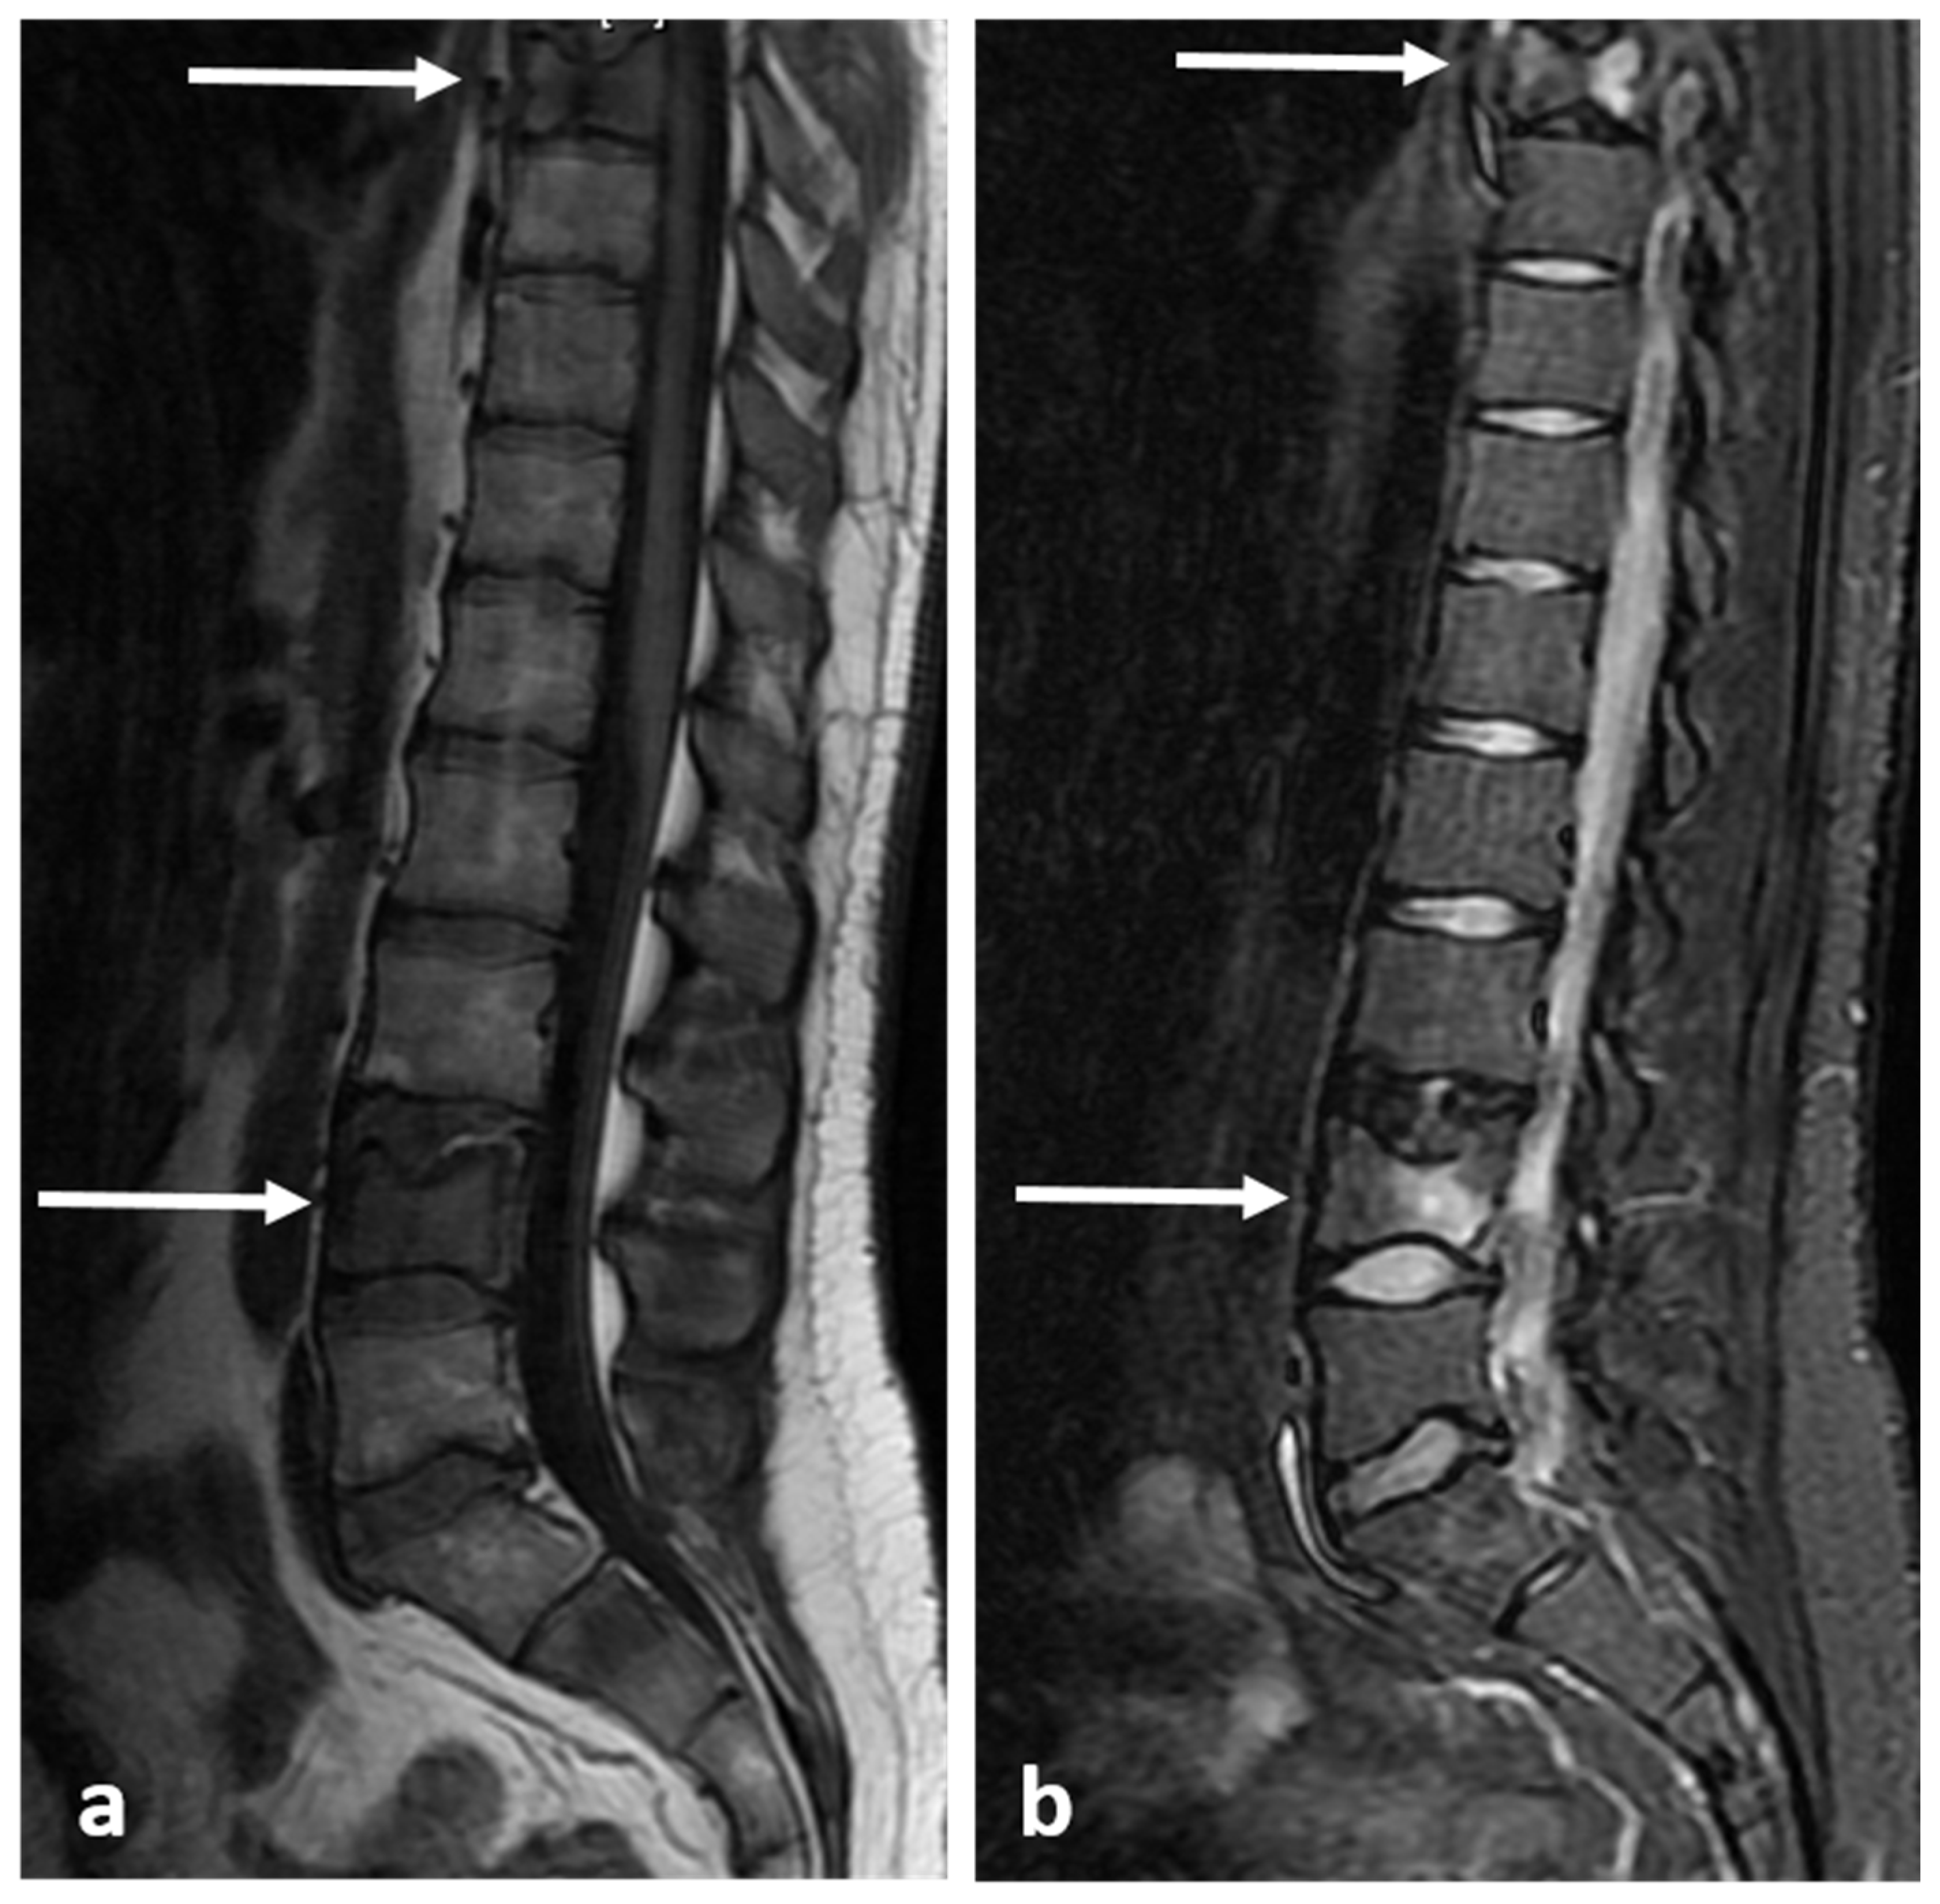

3.7. Haemangioma

| Haemangioma | Honey comb appearance. ‘Corduroy’ and ‘polka dot’ signs. | Usually T1 and T2 hyperintense due to fat content. Signal drop out >20% on out of phase chemical shift imaging. |